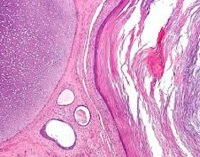

Параректальная дермоидная киста (параректальная кистозная тератома, пресакральная дермоидная киста, каудальная киста) - доброкачественное новообразование параректальной зоны, происходящее из эмбриональных клеток и содержащее в себе ткани-производные одного, двух или трех зародышевых листков. Чаще всего в полости параректальной дермоидной кисты обнаруживаются производные эктодермы: волосы, участки многослойного ороговевающего эпителия, элементы и содержимое сальных и потовых желез. Характерен медленный рост и доброкачественное течение. При образовании крупных кист возможно сдавление близлежащих органов. Малигнизация наблюдается у 8% пациентов. Лечение осуществляют специалисты в области проктологии и онкологии.

Большинство параректальных дермоидных кист представляют собой относительно простые однокамерные образования, содержащие только производные эктодермы. Такие кисты называют однолистковыми (представленные тканями, происходящими из одного зародышевого листка). В группе однолистковых неоплазий выделяют дермоидные и эпидермальные кисты. Реже встречаются двухлистковые параректальные дермоидные кисты, включающие в себя производные эктодермы и мезодермы или эктодермы и эндодермы, еще реже - трехлистковые, содержащие производные всех трех зародышевых листков.